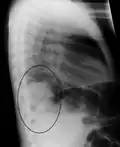

Right lower lobe pneumonia as seen on a lateral CXR

Normal lateral CXR -

The discovery of x-rays made it possible to determine the anatomic type of pneumonia without direct examination of the lungs at autopsy and led to the development of a radiological classification. Early investigators distinguished between typical lobar pneumonia and atypical (e.g. Chlamydophila) or viral pneumonia using the location, distribution, and appearance of the opacities they saw on chest x-rays. Certain x-ray findings can be used to help predict the course of illness, although it is not possible to clearly determine the microbiologic cause of a pneumonia with x-rays alone.